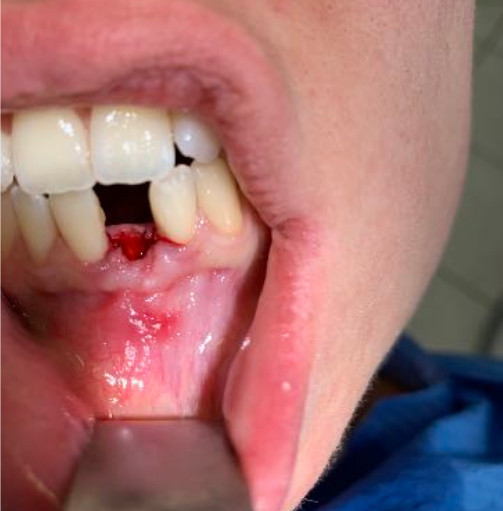

The reduced diameter of the neck allows you to protect yourself from any peri-implantitis and significantly improves the speed of healing. In this case it was tapped with a diameter of 4 and a Tramonte implant with a diameter of 4 mm with 7 threads with short neck was inserted. The titanium used is always grade 4.

| Welding: No | Dental area: lower incisor 31 |

| Extractive situation: Immediate post-extraction implant with immediate loading. | Density according to Misch: D2 |